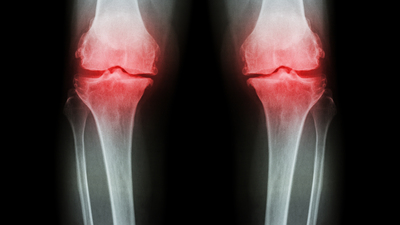

Daha az kemik dokusuna sahip oldukları için kadınların erkeklere göre osteoporoza yakalanma riski daha yüksektir. Kemik kalitesi ve yoğunluğunun azalması ile kemiklerin kırılgan hale gelmesine neden olan osteoporozu (kemik erimesi) doğru beslenme ile durdurmak ya da önlemenin mümkün olduğunu söyleyen Ortopedi ve Travmatoloji Uzmanı Prof. Dr. Çağatay Öztürk anlattı.

Osteoporoz vücudumuzda en çok omurgamızı etkiler. Osteoporotik kemiklerdeki kırıklar sıklıkla omurga, kalça ve el bileğini içerir. Kalça ve el bileğindeki osteoporotik kırıkların aksine omurgadaki kırıklar sıklıkla düşme veya travma ile ilişkili değildir. Vücutta sessizce ilerleyen ve kırık oluşmadığı sürece belirti vermeyen osteoporoz vakalarının sadece yüzde 30’u klinik şikayetler ile belirlenirken, geri kalan kısmın çoğu rastlantısal olarak saptanıyor. Hastalığın yaygın bulguları ise bel ve sırt ağrıları, boyda kısalma, omurgada kırık, sırtta kamburlaşma olarak ortaya çıkıyor.